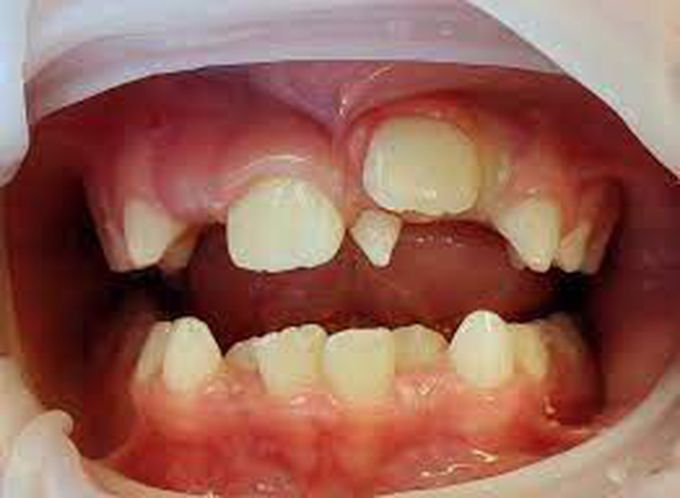

Dentists can diagnose hyperdontia during a routine examination. If extra teeth have erupted (grown in), they’ll be able to see them by looking inside your mouth. They can also take dental X-rays or CT (computed tomography) scans to see any impacted supernumerary teeth.